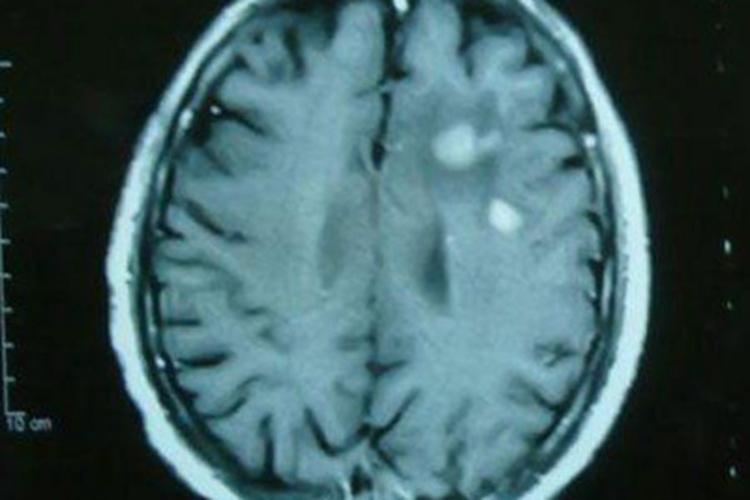

棘球蚴病可发生于头部,检查可见脑膜下散在的几个白色囊肿样物质,并同时存在几条线条状虫体,伴有头痛等不适感。其发展极其缓慢,潜伏期长,从感染至发病为10-20年或更长,多数患者在儿童期感染,成年期发病。